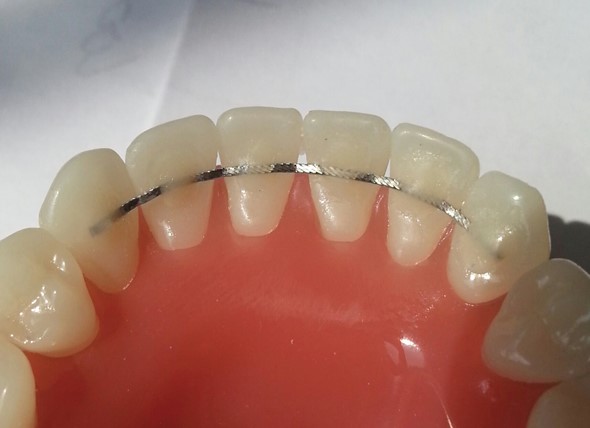

После брекетов обязательно ставят ретейнеры — металлические проволочки на передние зубы, с клыка по клык. Их не видно снаружи, они никак не ощущаются и не причиняют дискомфорта.

Ретейнеры нужно носить пожизненно, чтобы результат удерживался, а зубы не разъезжались.

Ретейнеры выглядят примерно вот так

Кроме того, пригодится ночная ретенционная капа на все зубы — в ней желательно спать ещё хотя бы год.